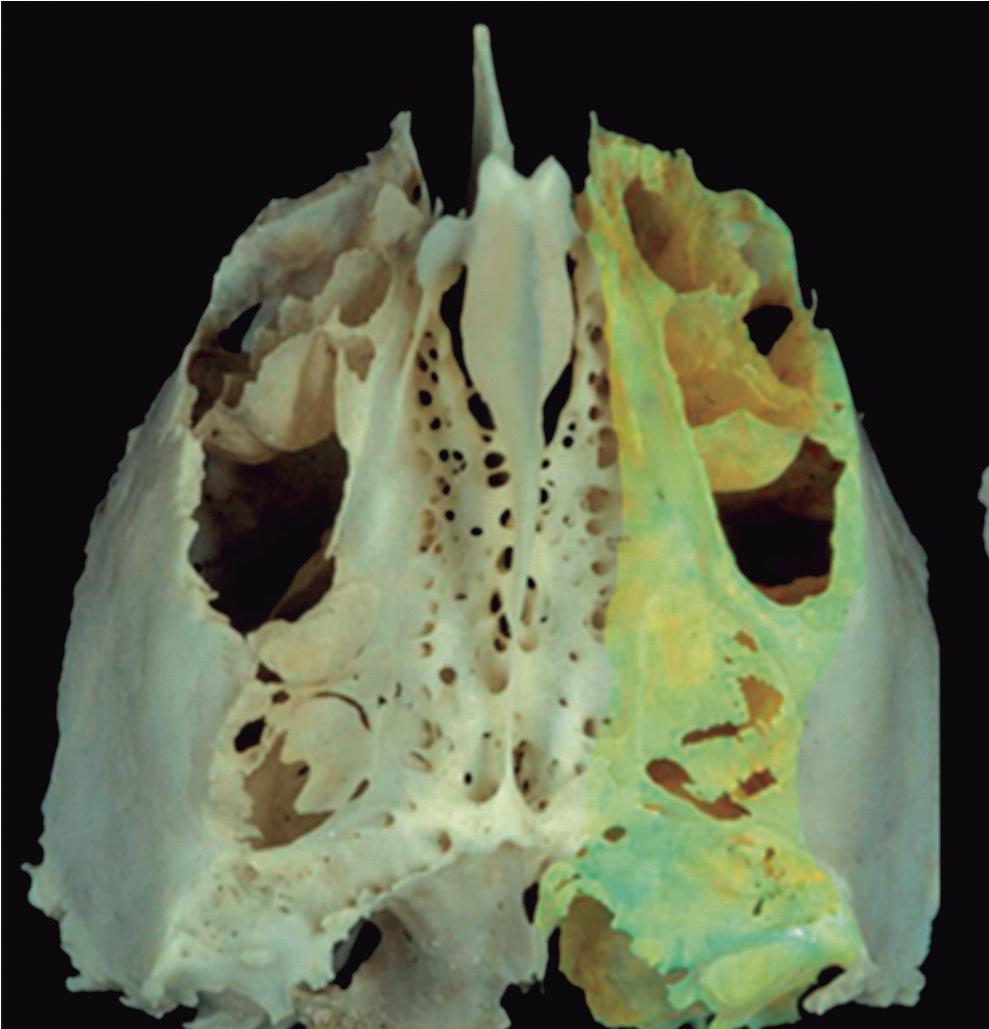

1-8. Osso etmoidal e seio etmoidal (amarelo) observar o aspecto incompleto do teto do seio etmoidal que será coberto pelo osso frontal (rosa).

As lamelas da placa das conchas são irregulares, tendo, com frequência, várias subdivisões, na maioria das vezes não paralelas e que formam no seu conjunto uma estrutura constituída por cavidades desiguais e definitivamente limitada pelo piso da fossa anterior, superiormente, e pela lâmina papirácea externamente. Por seu aspecto complexo esta estrutura por vezes é chamada de “labirinto”.

Fig. 1-45. Limites do seio etmoidal: (1) Limite anterior: junção da placa do agger nasi com o processo frontal do maxilar; (2) limite posterior: parede anterior do seio esfenoidal; (3) limite lateral: processo frontal do maxilar mais anteriormente, osso lacrimal (unguis) e a parede medial da orbita (lâmina papirácea) posteriormente; (4) limite superior: piso da fossa anterior, composto anteriormente pela parte medial do processo orbital do osso frontal e posteriormente pelo plano esfenoidal; (5) limite medial: estrutura vertical da concha média; (6) limite inferior: o seio etmoidal comunica-se livremente com a fossa nasal.